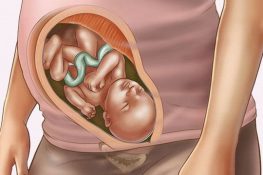

Mang thai là thiêng chức vô cùng thiêng liêng của người phụ nữ. Nhưng không phải chị em nào khi mang thai cũng nhận biết được hiện tượng có thai. Vì vậy nội dung bài viết dưới đây sẽ chia sẻ đến chị em 20+ hiện tượng có thai mà không phải ai cũng biết. Hãy theo dõi và cùng 2khoe tìm hiểu nhé!

20+ Hiện tượng có thai mà không phải chị em nào cũng biết

Khi mang thai cơ thể của nữ giới có nhiều sự thay đổi. Nếu chị em thường xuyên theo dõi bản thân thì không cần đến việc sử dụng que thử thai cũng có thể biết bản thân mình đã có thai hay chưa.

Dưới đây là một số hiện tượng có thai ở chị em, nếu thấy có thể xuất hiện những triệu chứng này. Xin chúc mừng chị em đã mang trong mình một thiên thần bé nhỏ đáng yêu.